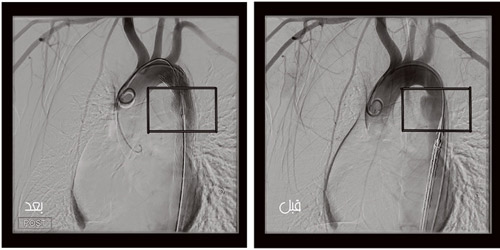

مضيفاً بأنه تم تحضير المريض وإجراء الإسعافات الأولية له، ثم نقل إلى وحدة الأشعة التداخلية المجهزة بأجهزة تصوير شعاعي حديثة «غرفة عمليات هجينة»، وبعد التصوير اللازم وجدت الإصابة على مستوى الشريان الأورطي الصدري النازل، وعلى الفور قام الأطباء المعالجين بإدخال دعامة اصطناعية عن طريق فتحه صغيرة في الفخذ، لا يتعدى طولها 1سم، وتم زرعها في الشريان الأورطي، وبذلك تم عزل الإصابة وترميمها لتستقر حالة المريض بعد العمل الجراحي. وأوصى الأطباء بإخراجه من العناية المركزة، ليستكمل ما تبقى من العلاج اللازم مع بقية التخصصات الأخرى بحسب الإصابة.

يذكر أن هذا العمل الجراحي من العمليات المعقدة التي يجرى لأول مرة بمنطقة جازان، وتم بمشاركة وحدتي الأشعة التداخلية، وجراحة الأوعية الدموية، وفريق التخدير في المستشفى.